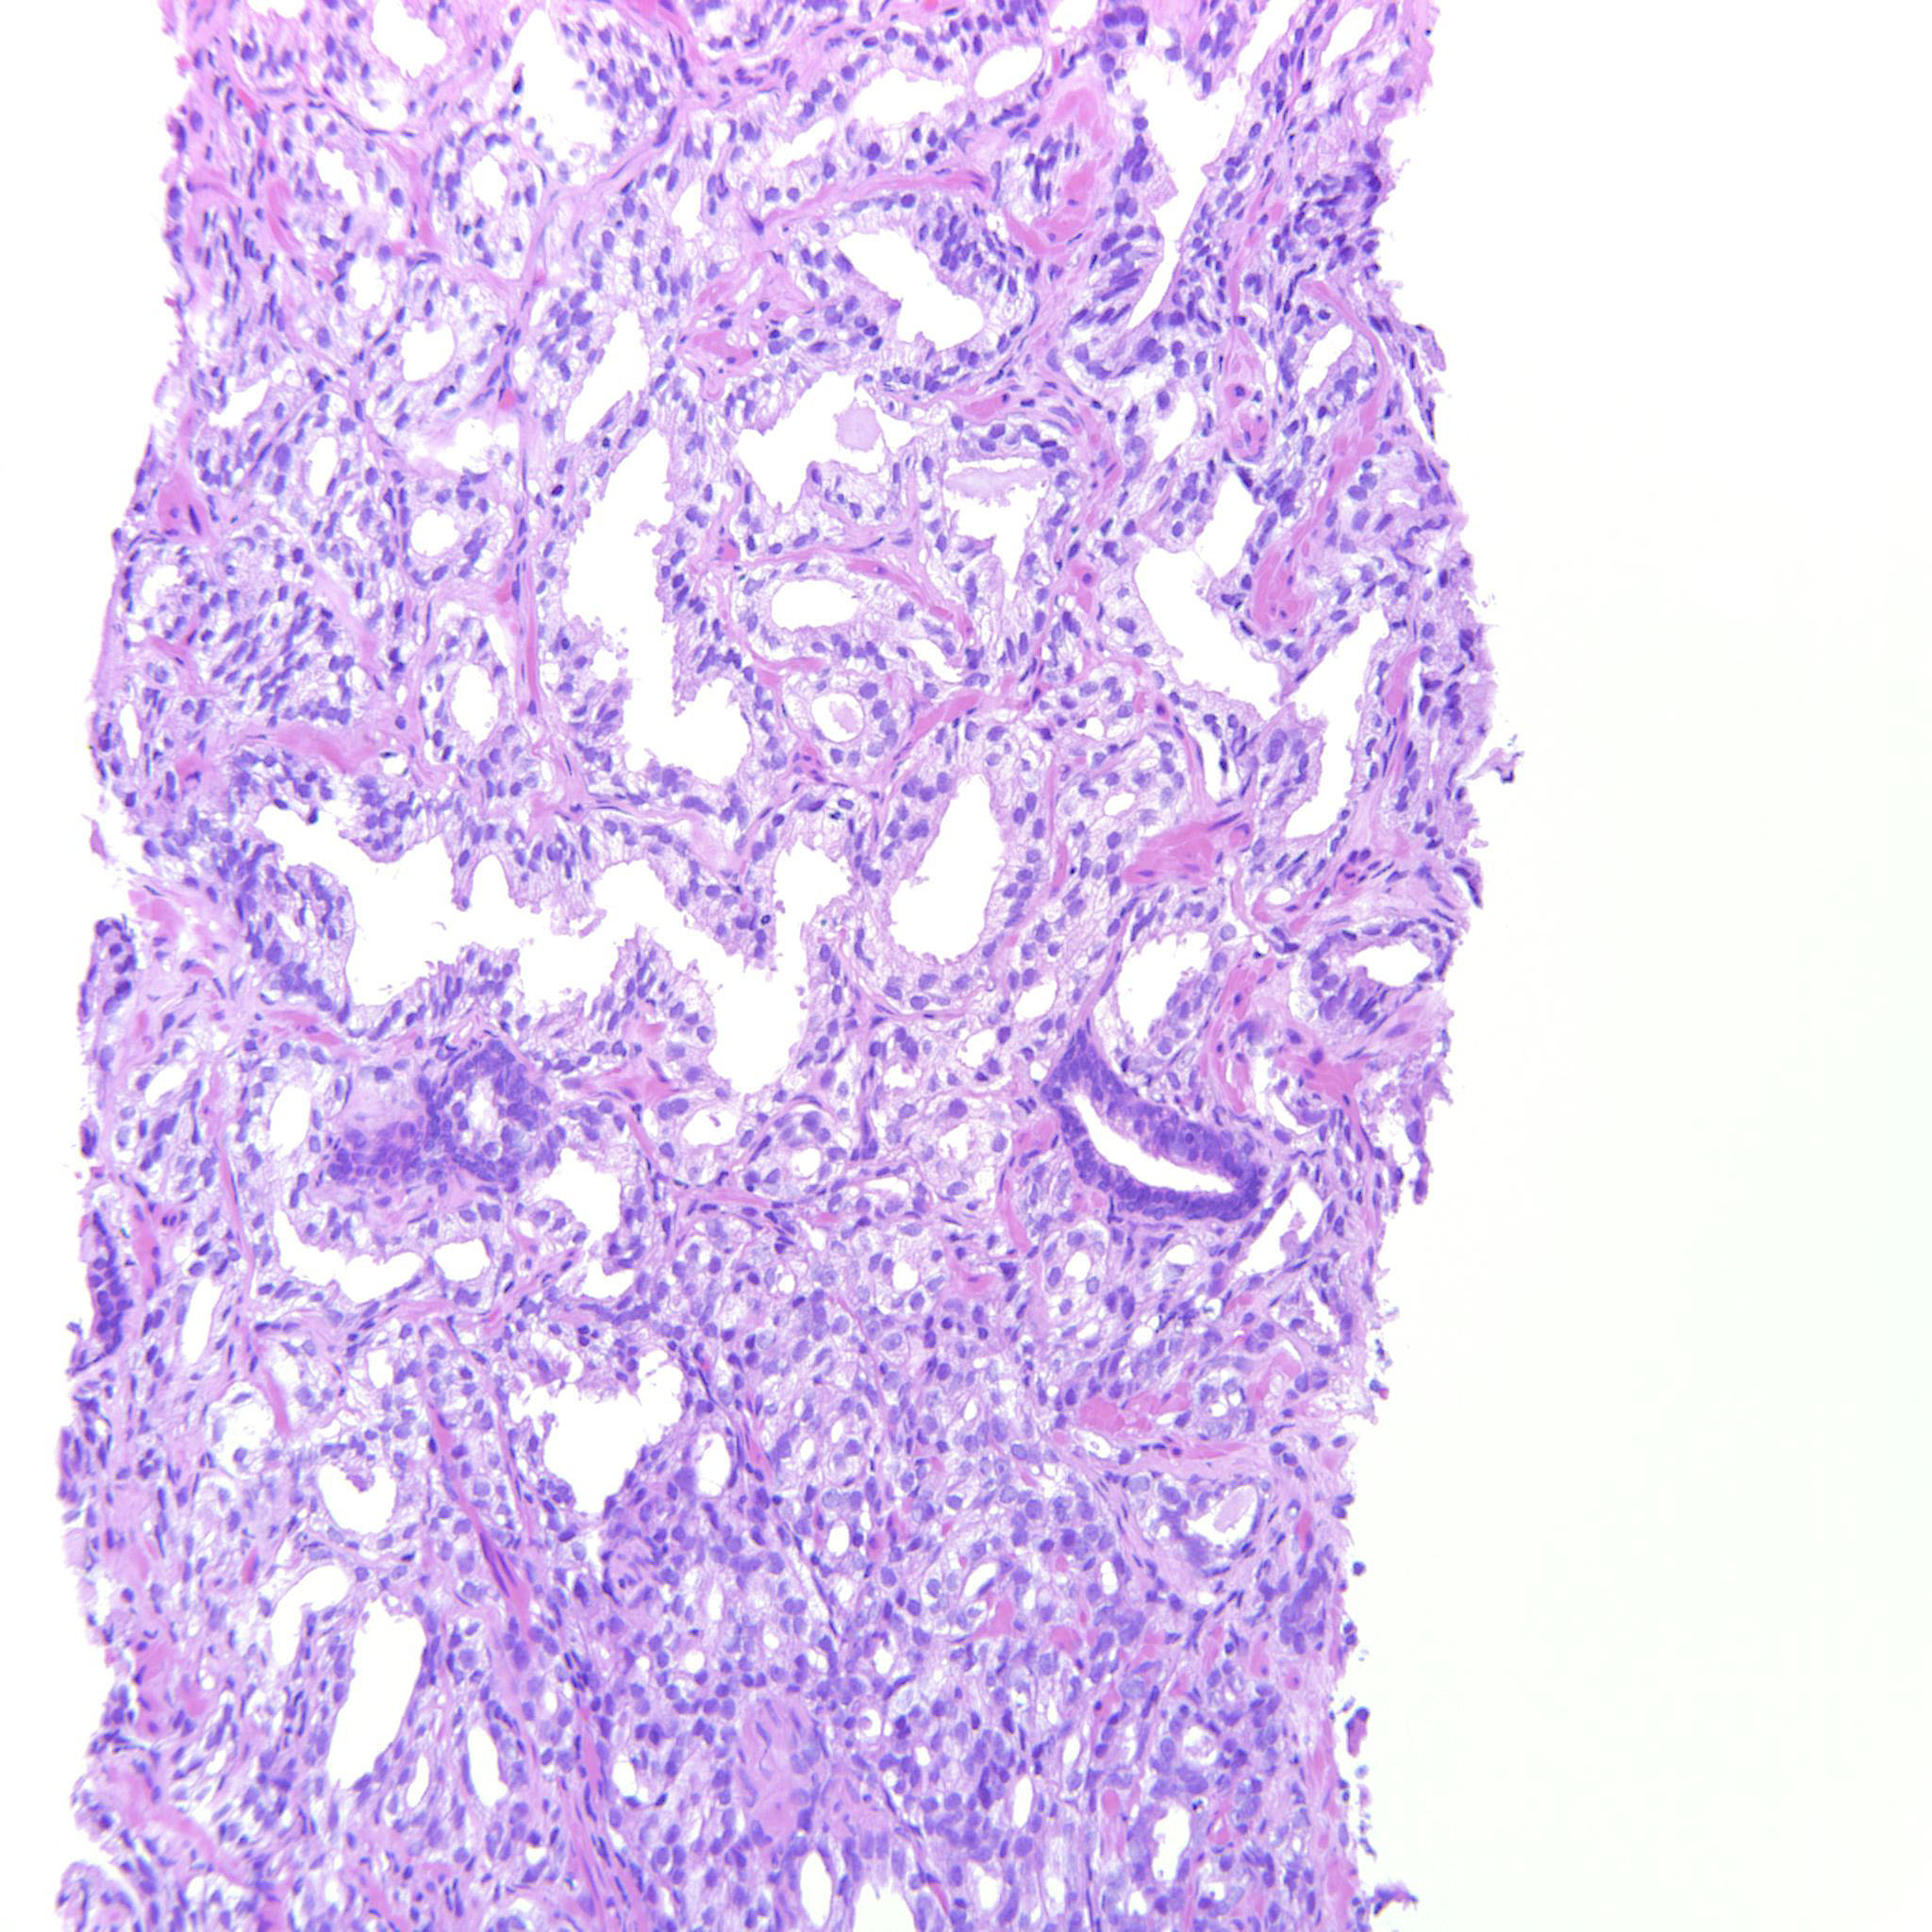

Prostate cancer grading

Case ID: 322